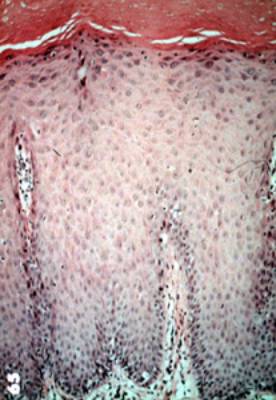

Microscopía de la displasia mucosa |

| Opuesta a la queratosis benigna, la displasia de la

mucosa ofrece anormalidades celulares significantes en el epitelio.

Esta microfotografía del epitelio escamoso normal,

que esencialmente es uniforme en un lado con una línea afilada de

demarcación entre este y el epitelio anormal en el otro. Incluso a

estos aumentos (resolución baja) uno puede descubrir la variación en

el tamaño, forma y pigmentación de las células. No hay ninguna invasión

del epitelio hacia el tejido conjuntivo. Esta es la característica que

distingue a la displasia de la mucosa del carcinoma espinocelular. |

Para repasar la diferencia entre el

epitelio normal y epitelio displásico usted debe comparar esta imagen

que es normal con la imagen anterior. |